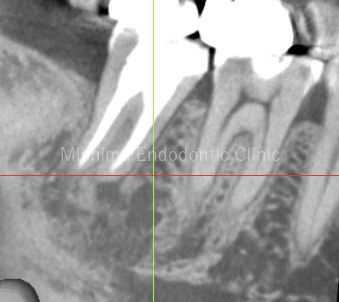

After

| 治療内容 | 既根管治療歯で比較的大きな根尖病変を認めた。根管治療は貼薬無しで即日根管充填。 術後、根尖透過像は消失し経過は良好。 |

術直後

術後1年